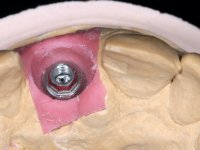

After performing an impression of the implant and making the models, we tested several rehabilitative options with the help of the implant brand planning kit. None proved capable. In this sense and as a resource solution, an innovative solution was proposed. It was proposed to make a milled Zr abutment with an appropriate design to receive a veneer that would hide the screw access hole. The veneer itself had a ceramic-coated Zr infrastructure. The goal was to achieve retention and strength by screwing the abutment and aesthetically solve the case with the veneer.

After the impression of the implant using a double-mix technique with double viscosity and the collection of shape and color information by the ceramist, we proceed with the work. In the model, a syn octa was placed over the implant, and a screw was placed on it to assess its emergence in relation to the incisal edge. Then, an adequate emergence profile in the artificial gingiva was prepared. A abutment with characteristics suitable for overbite and simultaneously capable of receiving a veneer was waxed on top of this scenario. This waxing gave rise to the manual milling of a very personalized abutment. An infrastructure in Zr was also made for the veneer with a very great adaptation to the abutment. On this infrastructure ceramics were placed. Ceramic fluorescence sought to compensate for the lack of fluorescence that Zr had and obviously further customize the aesthetics. The adhesive bridge was removed and the definitive work was placed. The syn octa was initially tightened with 35 N to the implant and then the Zr abutment was tightened over the syn octa with 15 N. The access hole was plugged and then the veneer was cemented with resin-reinforced glass ionomer. After 15 years, the patient returned to the consultation with tooth mobility. Fortunately, nowadays we have the possibility of having dynamic tightening wrenches that allow tightening screws with greater inclinations. An access cavity was made without damaging the incisal edge of the veneer. Tightening was done with a dynamic wrench with 15 N torque. The hole was covered with Teflon and filled with composite resin. This solution allowed the problem to be solved in a simple and economical way.